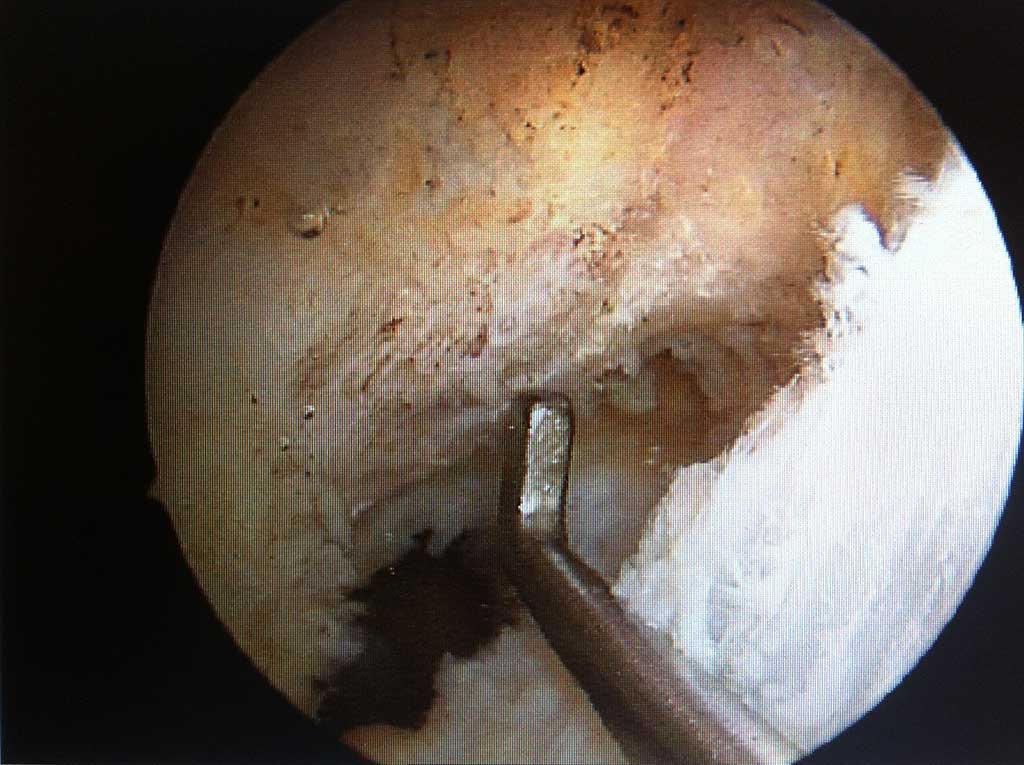

Knorpel-Knochen Übertragung ( OATS, "Mosaikplastik")

Wie läuft die Operation ab ?

Dieser knorpelwiederherstellender Eingriff wird bei geeignetem isolierten, eher kleineren Knorpelschaden entweder arthroskopisch oder "mini open" unter stationären Bedingungen durchgeführt. Es werden dabei aus einem minimal belasteten Areal des betroffenen Kniegelenkes ein oder mehrere Knorpel-Knochen Zylinder entnommen und diese dann in " press fit " Technik in den speziell vorbereiteten Knorpeldefekt in der Belastungszone übertragen. Die Einheilung ist im wesentlichen in 6-8 Wochen abgeschlossen ( Knochen - Knochen Heilung ) und in dem Defekt befindet sich ein original Gelenkknorpel. Die Entnahmestellen füllen sich mit Faserknorpelgewebe.

Diese Operationstechnik verlangt eine sehr große Erfahrung des Operateurs und sollte daher nur durch Kniespezialisten mit Expertise in der gelenkerhaltenden Chirurgie durchgeführt werden!